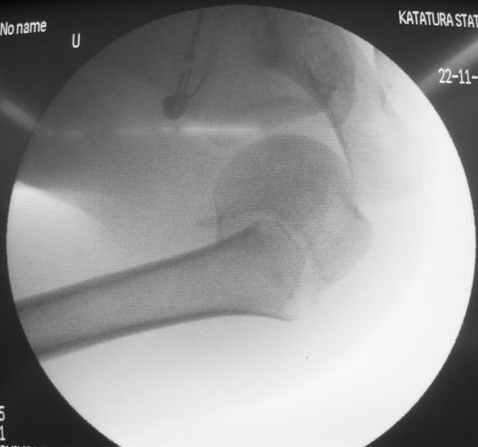

Коллеги, Больной прооперирован вчера. 19 летний пациент с переломом шейки плеча. Закрытая репозиция и чрескожная фиксация спицами под контролем ЭОПа ( техника проф. Лазарева)

Интраоперационный контроль на стабильность фиксации - сомнений в стабильности фиксации не возникло. Послеоперационный контроль сегодня......

Необходимость послеоперационного Рг контроля..... Больной запланирован на повторную манипуляцию и транспозицию спиц Евгений И Чекашкин